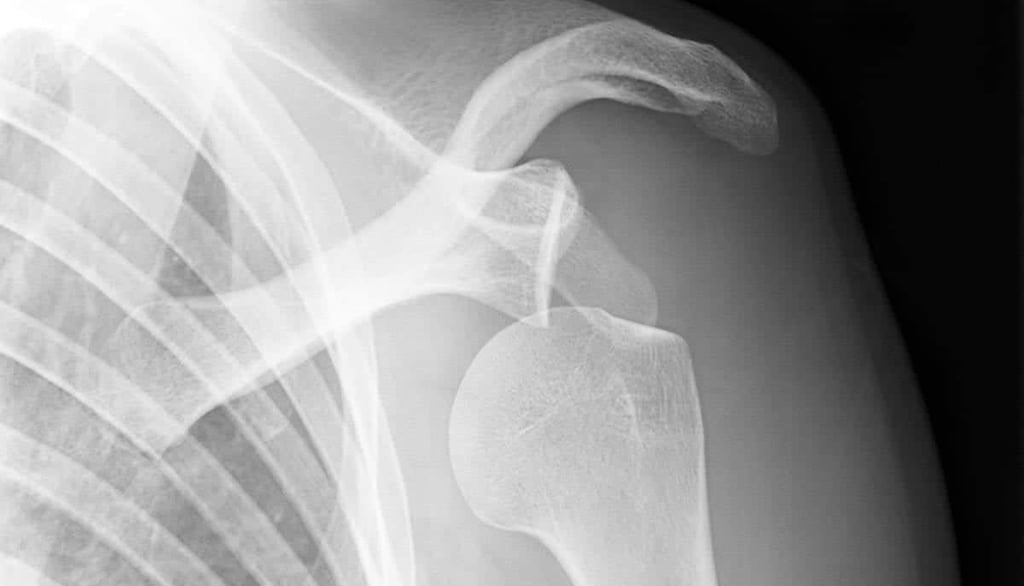

Comprendre l'Instabilité de l'Épaule

L'instabilité de l'épaule est une condition courante qui résulte souvent d'une luxation. Cette pathologie peut sérieusement compromettre l'articulation de l'épaule, entraînant des douleurs et une incapacité à réaliser des mouvements quotidiens. Les luxations peuvent survenir lors d'activités sportives intenses, d'accidents, ou même d'un mouvement banal, engendrant ainsi une instabilité qui nécessite une intervention médicale appropriée.

Le traitement des luxations de l'épaule varie considérablement en fonction de la gravité de la condition. Dans les cas les moins graves, on recommande souvent une approche conservatrice, comprenant le repos, la physiothérapie et le port d'une attelle. Cependant, lorsque l'instabilité persiste, il devient capital d'envisager des interventions chirurgicales. Ces procédures visent à stabiliser l'articulation et peuvent inclure des techniques comme la butée de Bankart, qui rétablit l'intégrité de la capsule articulaire.